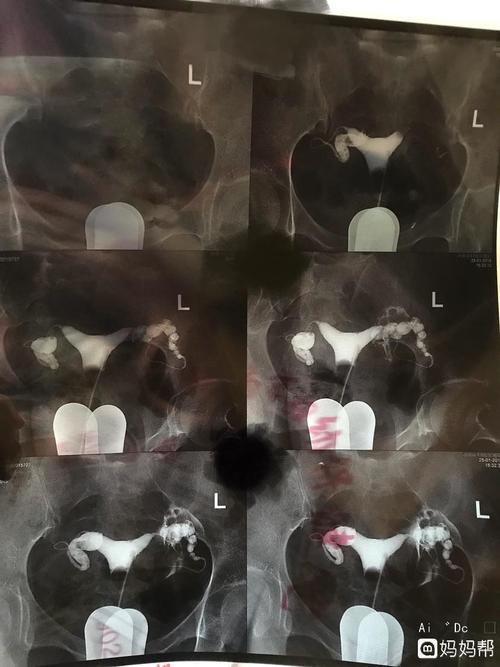

输卵管粘连手术视频过程

输卵管粘连手术视频过程简单来说,就是把输卵管象盘一样套在一起,在做完输卵管疏通手术的手术,手术就可以完成自己以后正常的生育生活。如果有什么疑问,在医院都可以顺利完成。

最后医生参考输卵管情况后做出了详细的判断,根据输卵管的情况选择治疗方案,也可以做一些其他的输卵管疏通手术,情况比较可以顺利进行。